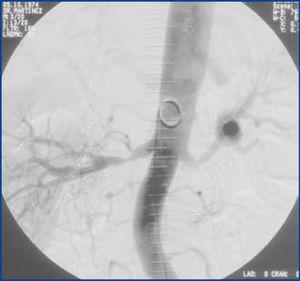

Posteriormente, se objetivó un deterioro importante de función renal: creatinina (Cr) 3,7 mg/dl, aclaramiento de creatinina (ClCr) 26,35 ml/min, que mejoró parcialmente tras suspender el inhibidor de la enzima de conversión de la angiotensina y el antagonista de los receptores de angiotensina II. Dada la sospecha de HTRV, se realizó una angiorresonancia magnética abdominal confirmando la presencia de estenosis en arteria renal derecha a 11 mm del óstium y un aneurisma ovoide en la porción terminal de la arteria renal izquierda, con diámetro mayor de 1,8 cm. Seguidamente, se realizó una arteriografía renal, donde se objetivó estenosis bilateral de arterias renales de probable origen fibrodisplásico (figura 1). Ante los hallazgos, se realizó angioplastia transluminal percutánea bilateral, con recuperación ad integrum de la función renal: Cr 1 mg/dl, ClCr 80 ml/min y TA controlada con triple terapia antihipertensiva (labetalol 300 mg/día, amlodipino besilato 10 mg/12 h, torasemida 5 mg/día).

Figura 1. Arteriografía